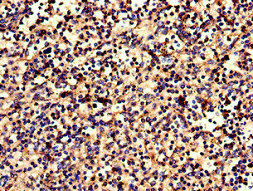

Immunohistochemistry of paraffin-embedded human spleen tissue using CSB-PA005679LA01HU at dilution of 1:100